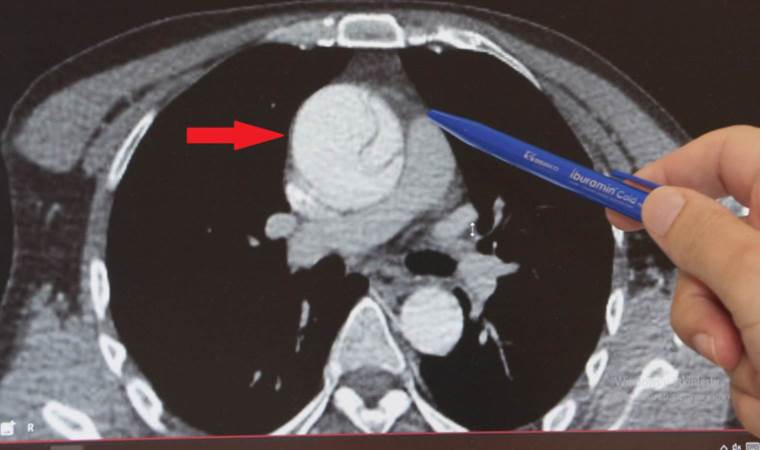

Yusuf Toplusoy’un yıllar önce aort damarındaki genişleme nedeniyle tedavi edilip, sonrasında kontrollerini azalttığını vurgulayan Prof. Dr. İsbir, “Karın bölgesindeki anevrizma göğüste de tespit edildiği için bize geldi. Eş zamanlı olarak hastanın şah damarlarını da kontrol ettik ve şah damarında yüzde 95 darlık tespit ettik. Hastanın önce şah damarını sonra da göğüs anevrizmasını tedavi ettik” dedi.

Hastada yüzde 95 şah damarı tıkanıklığı bulunduğunu ve felç riskinin de yüksek olduğunu anlatan Prof. Dr. İsbir, “Aort damarı 6 santimetreyi aşıyordu. Hasta hem felç hem ciddi anevrizma patlaması ile hayati bir risk ile karşı karşıyaydı. Hastamız gerekli takiplerini aksatmış. İlk ameliyatını gerçekleştirdikten sonra sigara içmeye devam etmiş ve hastalığı ilerlemiş. Yusuf Bey örneğinde olduğu gibi damar sertliği olan hastalar “ameliyat olduk her şey bitti” yanılgısına kapılmamalı. Risk faktörünü devam eden durumlara devam ettiklerinde 2,3,4’üncü ameliyatı da olabilirler” dedi.